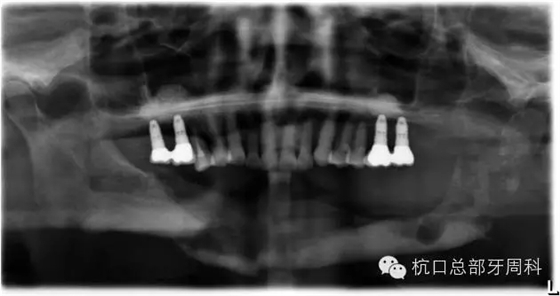

種植后即刻拍片 2005

110.webp.jpg